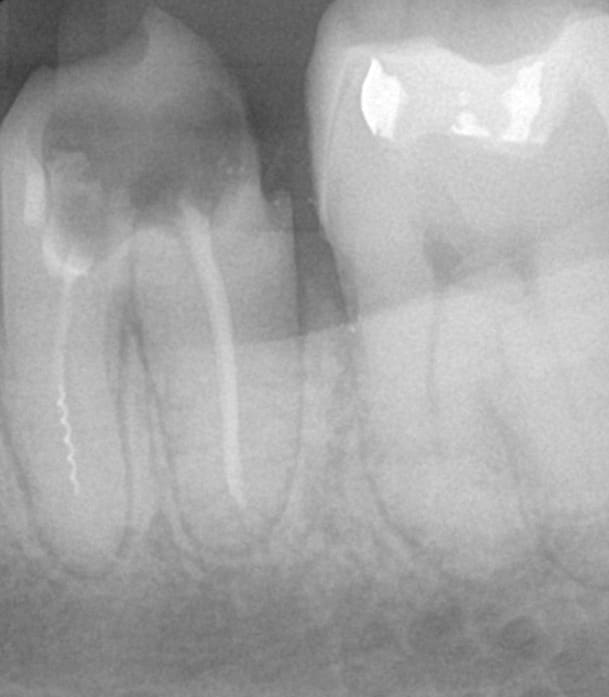

Patient d'une petite soixantaine d'années. Brossage correct et brossettes. Pas de prothèse inférieure.

Il y a un "contrat" sur la 26, pas sur les voisines. Et il ne fallait pas mettre d'implant pcq la zone 11-21 est électriquement anormale. Perdu d'avance.

Cette hypothèse électrique permet peut-être de comprendre pourquoi cette dent couronnée il y a 25 ans est asymptomatique. Le cône distal est mobile, mais pas le lentulo.

La 26 égressée m'interpelle pcq les autres n'ont pas bougé alors quelles n'ont pas d'antagonistes non plus depuis longtemps.

Bien d'accord junior, mais le calage se fait sur les 4 depuis 20 ans et les latérales, moins bien plantées que les centrales en principe, ne se portent pas trop mal.

Je suis entièrement d'accord avec toi, mettons lui des dents en bas, mais je me dis quand même que c'est bizarre que les latérales ont tenu le coup. L'implant tient toujours très bien sur les 2 ou 3 mm qui restent. La centrale n'est pas en contact avec son antagoniste, mais bon, ça ne va sans doute pas évoluer favorablement...